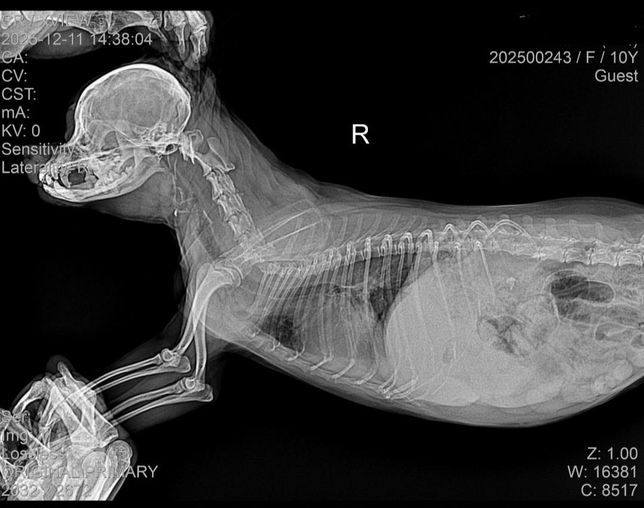

- 반려동물 건강반려동물탈퇴한 사용자강아지 폐수종 상태 확인 부탁드립니다.전에 목에 이물질이 걸려 이를 제거하는 과정에서 비심인성으로 폐에 물이 약간 차 이뇨제를 투약하고 입원을 시켰습니다.하지만 입원 다음 날, 폐에 물은 빠지지 않고 신장 수치만 하루 새 30이 증가했습니다. 이에 이뇨제 투약을 중단하고 경과를 지켜보기로 했습니다.그 다음 날, 신장 수치는 약 10 정도 낮아졌고 폐에 찬 물도 조금 빠졌다고 했습니다. 그래서 그 다음 날 퇴원을 계획했으나, 당일 아침 다시 확인해 보니 폐에 물이 더 찼다고 했습니다.병원 환경이 불편한지 배변을 잘 하지 못하고 있습니다. 다만 현재 신장 수치는 32이고, 호흡수도 나쁘지 않으며 식욕도 있는 편입니다. 병원에서 스트레스를 더 받게 두기보다는 집에 데려와 지켜보고 싶은데 괜찮을지 궁금합니다.아래 사진은 입원당시 사진입니다.1명의 전문가가 답변했어요